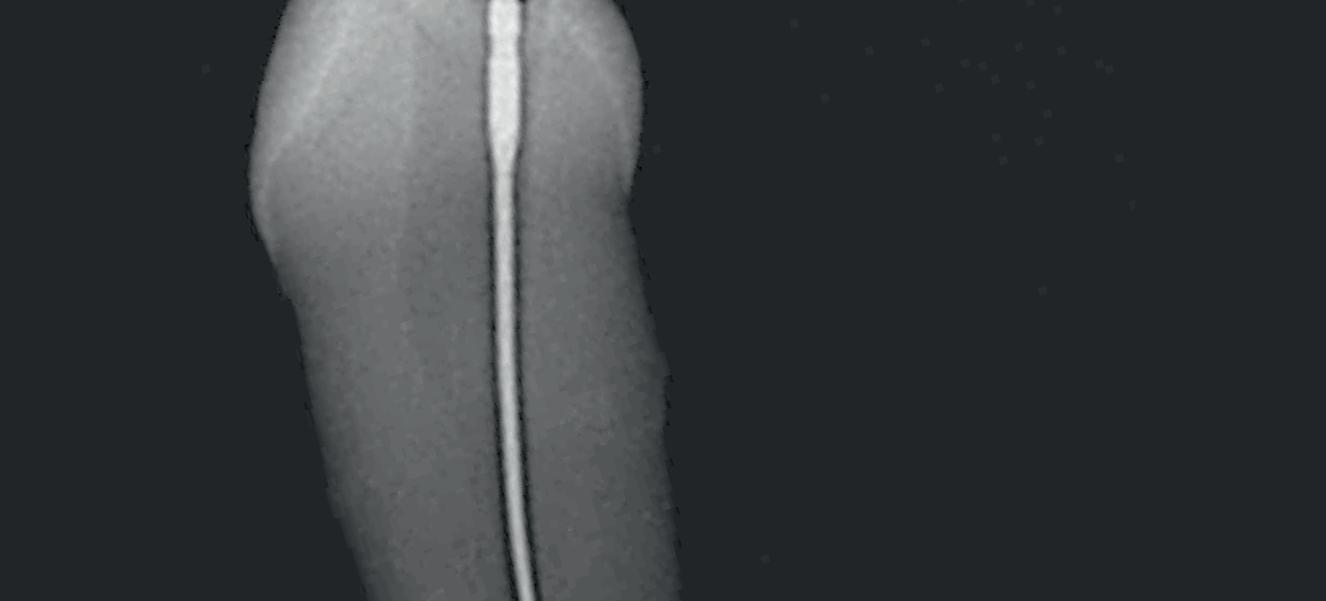

Tri Auto ZX2+

CCW CW CW CCW File example Mode Sequence CW CCW 3